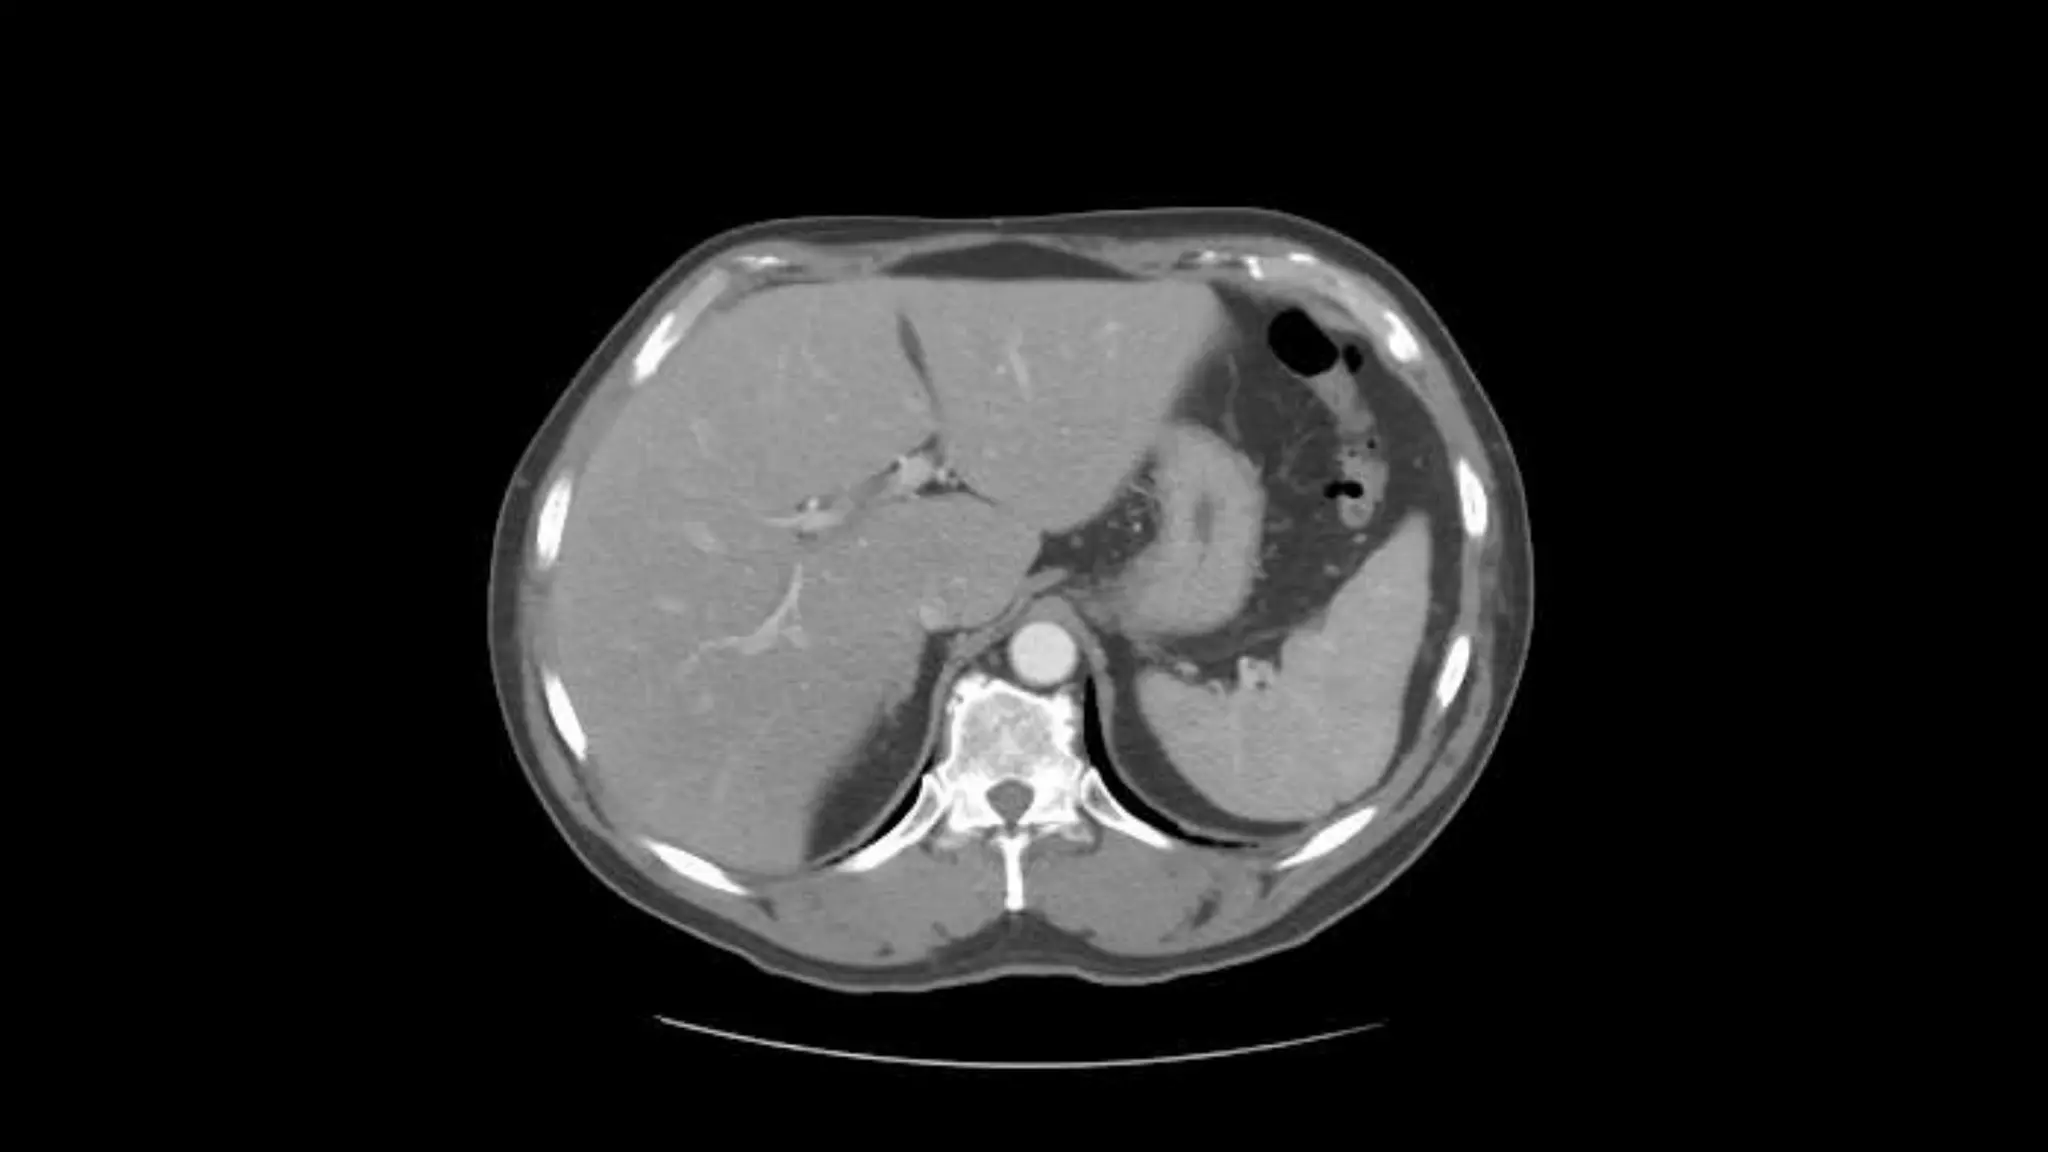

 In this sequence of images, we will label the abdominal vasculature.

The CT images are 5mm slices with soft tissue window settings. IV

Follow the IV contrast filled Aorta as we descend caudally. Branches and points

of interest will be noted.